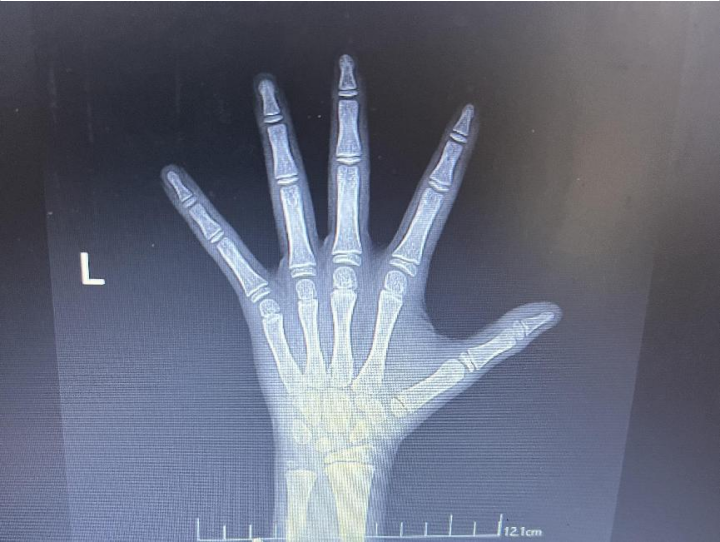

儿保科李慧娟主任表示:想要了解孩子是否能长高,骨龄是个关键指标。若担忧孩子身高发育不足,除了常规测量身高外,更精准的方法是检查骨龄,即观察骨骺的闭合情况。但需注意的是,对于年纪过小的孩子,骨龄检查可能无法准确反映问题,通常建议4岁以上的孩子进行此项检查。

在孩子的成长过程中,骨龄检查的频率可以根据年龄和发育情况进行调整。一般来说:

从4岁到青春期前,每年进行一次骨龄检查是合适的;

进入青春期后,建议每6个月检查一次。

对于性早熟的孩子,骨龄检查的频率可以提高至每4-6个月一次。